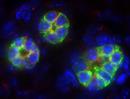

| Immunofluorescence of mutant 012-029-LA collecting duct | Cplane1b2b012Clo/Cplane1b2b012Clo | C57BL/6J-Cplane1b2b012Clo |

| Immunofluorescence of mutant 012-029-LA ureteric bud. Cilia in ureteric buds and collecting ducts are shorter than normal | Cplane1b2b012Clo/Cplane1b2b012Clo | C57BL/6J-Cplane1b2b012Clo |